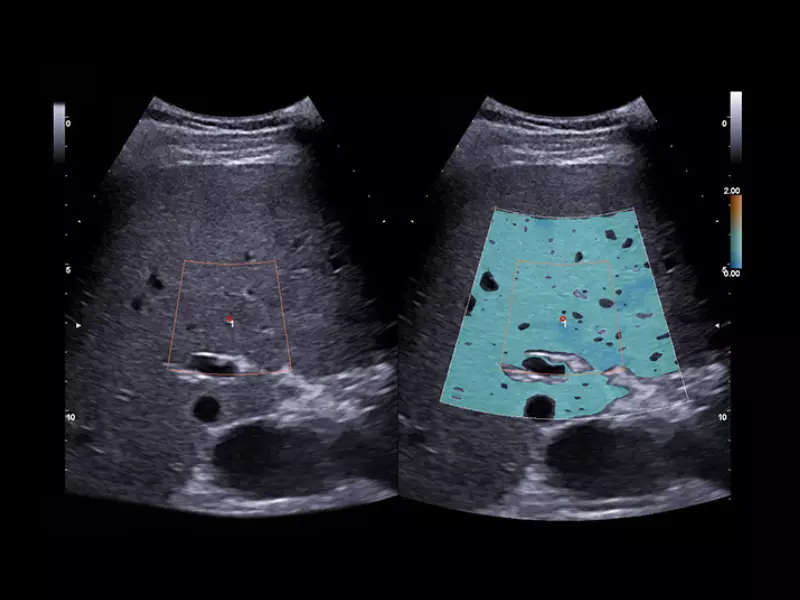

MyLab™9 Platform - XFlow Doppler enhancement in liver vascularization

MyLab™9 Platform - XFlow Doppler enhancement in liver vascularization

MyLab™X9 - Liver 01

MyLab™X9 - Liver 01

MyLab™X9 - Liver 02

MyLab™X9 - Liver 02

MyLab™A50 - Liver BMode

MyLab™A50 - Liver BMode

MyLab™A70 - Liver pathology

MyLab™A70 - Liver pathology

MyLab™A70 - Liver Bmode

MyLab™A70 - Liver Bmode